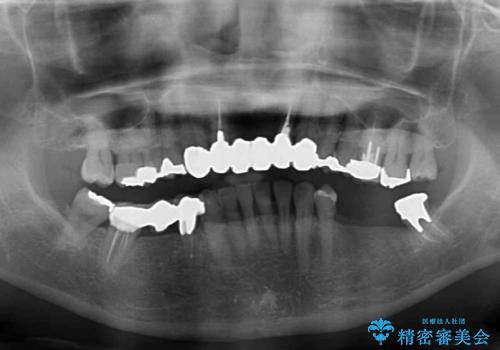

- 口の中に気になるところが沢山あるものの、地元ではなかなか治療を行ってくれるところがないとのことで、沖縄県の離島より来院された患者様です。

金属を使用した前歯のブリッジや奥歯の銀歯は全てオールセラミッククラウンまたはセラミックインレーとし、左下の奥歯はインプラントにより治療を行うこととしました。

外科処置を行うため、治癒を待つ期間が数ヶ月あるため、その期間を利用して下顎前歯のスペースを矯正治療で閉じることとしました。